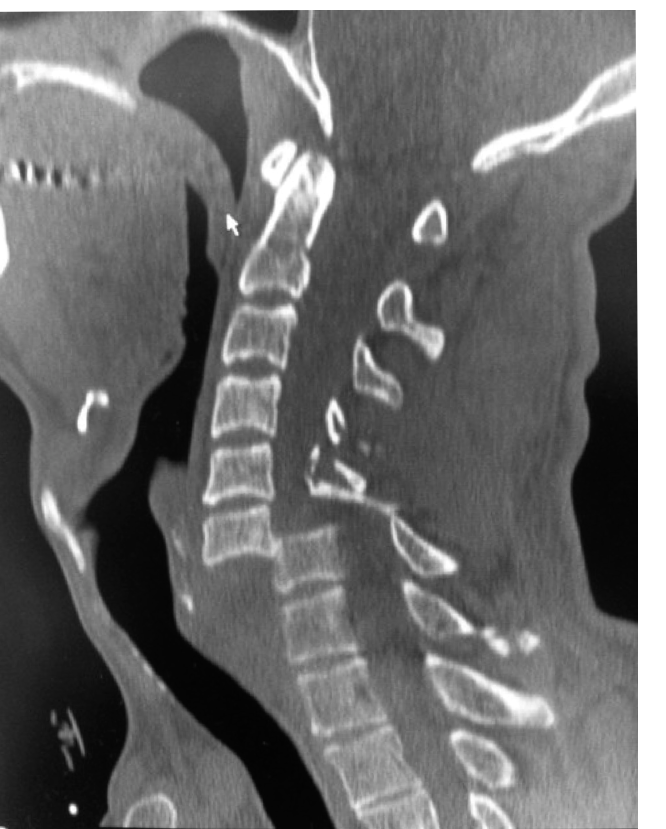

A 20-year-old man is brought to the emergency department following a high-speed road traffic accident in whic…